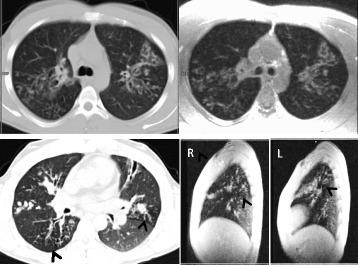

Bronchiectasis is a common feature of severe inherited and acquired pulmonary disease conditions. Among inherited diseases, cystic fibrosis (CF) is the major disorder associated with bronchiectasis, while acquired conditions frequently featuring bronchiectasis include post-infective bronchiectasis and chronic obstructive pulmonary disease (COPD). Mechanistically, bronchiectasis is driven by a complex interplay of inflammation and infection with neutrophilic inflammation playing a predominant role. The clinical characterization and management of bronchiectasis should involve a precise diagnostic workup, tailored therapeutic strategies and pulmonary imaging that has become an essential tool for the diagnosis and follow-up of bronchiectasis. Prospective future studies are required to optimize the diagnostic and therapeutic management of bronchiectasis, particularly in heterogeneous non-CF bronchiectasis populations.

支气管扩张症是严重遗传性和获得性肺部疾病的常见特征。在遗传性疾病中,囊性纤维化(CF)是与支气管扩张症相关的主要疾病,而获得性疾病常伴有支气管扩张症,包括感染后支气管扩张症和慢性阻塞性肺疾病(COPD)。从机制上讲,支气管扩张症是由炎症和感染的复杂相互作用驱动的,中性粒细胞炎症起着主要作用。支气管扩张症的临床特征和管理应包括精确的诊断性检查、量身定制的治疗策略和肺部成像,这已成为支气管扩张症诊断和随访的重要工具。需要前瞻性的未来研究来优化支气管扩张症的诊断和治疗管理,特别是在异质性非 CF 支气管扩张症人群中。